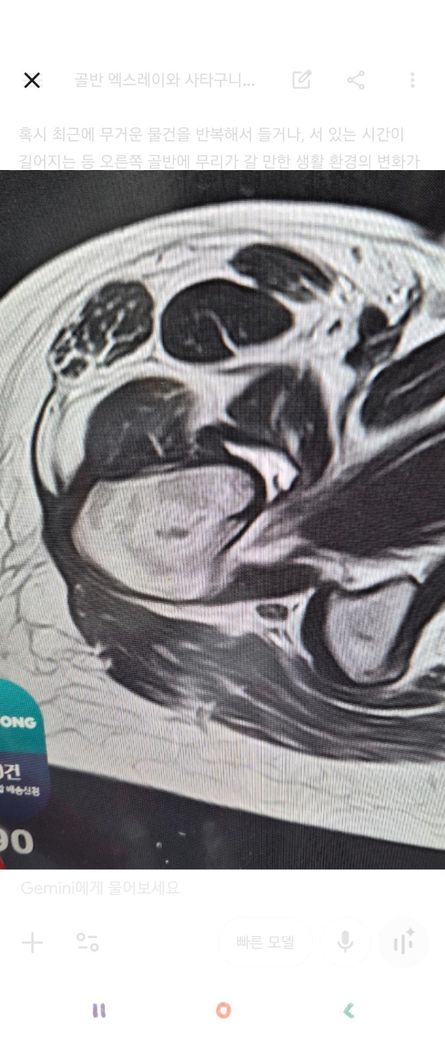

가동범위 제한이 있어 엠알아이를 찍었는데..

문제될만한게 있을까요?

윤활막액염?인가 그렇다는데

낫지를 않아요ㅜㅜ

1월달에 아파서 현재까지 차도가없어요..

• 2번 째 사진

사진만으로는 정확한 판독이 어려울 수 있기 때문에 관련 진료과목 전문의에게 대면진료를 받아보시는 것이 좋겠고, 점액낭염이나 윤활막염으로 인해서 발생하는 통증과 움직임 제한이 오래 지속될 수 있습니다.

우선 현재로썬 판독 받으신대로 윤활막액염의 가능성이 있으며 1월부터 통증이 지속된다면 전문의와 상담을 통해 주사치료, 체외충격파, 도수치료 등 다른 치료들도 병행 해보시길 추천드립니다.

또한 당분간은 무리하게 움직이거나 자극을 주는건 피하시고 호전이 없다면 필요에 따라 전문의와 상담 후 상급병원 진료도 고려해보시길 바랍니다^^